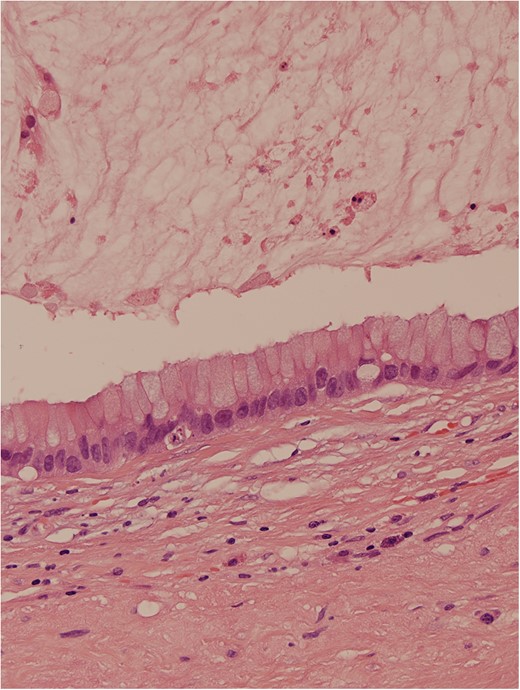

Haematoxylin and eosin stain demonstrated a mucin-containing cyst, lined by a partly detached columnar epithelium containing numerous goblet cells, surrounded by a dense, lightly inflamed fibrous stroma and a thin rind of calcified tissue probably representing residual pineal gland. The epithelium lining the cyst comprised cuboidal and columnar epithelial cells largely arranged as a monolayer, but with focal stratification, mild cytologic atypia and rare mitoses, but no malignant change. The cyst contained copious mucin, with an inflammatory and histiocytic reaction. Dystrophic calcification was present, both within the cyst and in the dense fibrous wall. Immediately peripheral to the main central cyst, there were a few smaller outpouchings into the stroma lined by epithelium of similar nature. No other germ cell elements were identified. The features were interpreted to represent mature cystic teratoma with only a monodermal tissue element (mucinous, cystic glandular element), with no other neoplastic germ cell component, most probably of pineal origin.